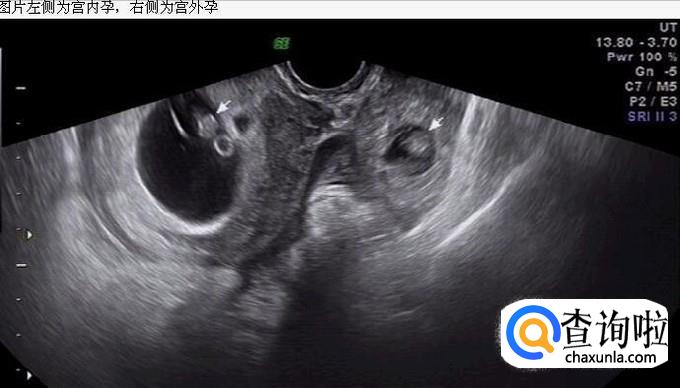

做B超检查。如果在宫腔镜看到孕囊,就可以排除宫外孕的。

如果是宫外孕的话,在B超下我们可以看见宫腔外有囊肿或混合性包块,并且宫内没有孕囊。